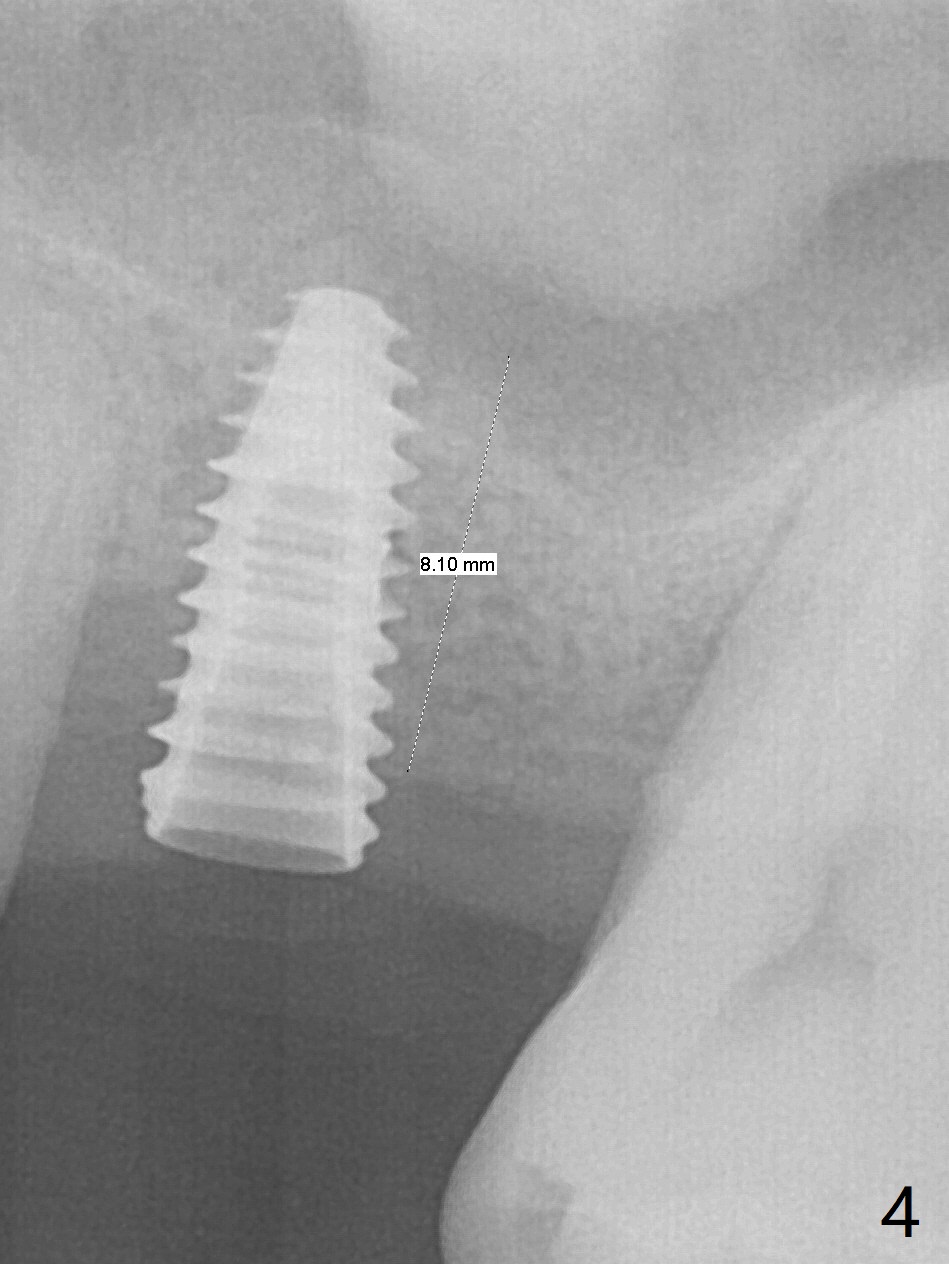

Trajectory of sinus lift without guide at #14 is off (Fig.1 (Magic Sinus Lifter (L) for 9 mm (gingival level)) and needs to be corrected (Fig.2 long line) by re-using 4.8 mm Magic Drill. Following placement of PRF membrane and Demineralized Cortical Allograft (.125-.850 mm) for sinus lift (Fig.3 black dashed line), a 4x10 mm dummy implant is placed with off trajectory. The latter will be fixed by using Lindmann bur to remove the bone distal (Fig.4). The result is less satisfactory with placement of 4.5x10 mm dummy implant (Fig.5). It appears necessary to initiate a new osteotomy (Fig.6 long black line). In fact the result is appealing (Fig.7). The final implant (5x7.3 mm) seems to be placed ideally shown by PA (Fig.8) and BW (Fig.9). Immediately postop CT demonstrates distal defect (Fig.10 *;3-D) and supracrestal placement palatal (Fig.11 P; coronal section). More allograft is then placed in these 2 areas. In all, it is difficult to establish a correct osteotomy without guide. The patient return for uncover 3.5 months postop, although there is a small hole in the middle of the incision (Fig.12). The crown/abutment becomes loose less than 1 month post cementation when the patient chews something tough. It is more related to the unfavorable implant/crown ratio. It is loose again 2 months later. Screw driver is buried inside the abutment with plumber tape. When it is loose for the 3rd time 13 months post cementation, the existing screw driver with a created slot (for retention) is buried without plumber tape after retorque at 35 Ncm (Fig.13). A tissue-level implant should have been used.